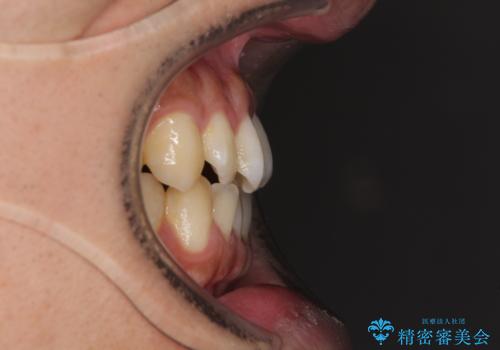

- 上下の前歯の叢生を気にして来院された患者様です。

前歯のみの矯正治療を希望でしたが、上顎臼歯が舌側転位していたため、上顎は全体を、下顎は前歯のみを矯正治療することとしました。

矯正治療は上下全顎を行うことが大前提ですが、費用などの点から、今回は部分矯正を選択することとなりました。

患者様本人は咬みにくさを感じていないようですが、部分矯正は咬み合わせの改善が困難であることが多く、咬みにくさが残ることがあります。